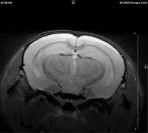

Small Animal Multimodal Imaging

Magnetic Resonance